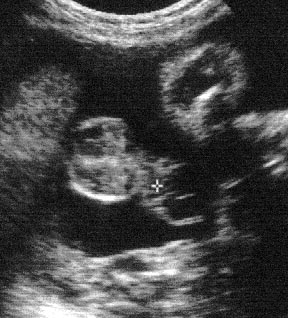

الولد

ولد في الأسبوع ال 15

ولد في الاسبوع ال16

الأسبوع ال17

الأسبوع ال18